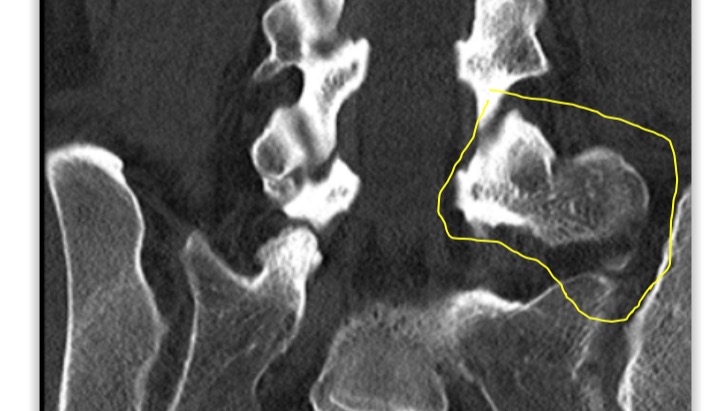

This disorder causes bone-to -bone contact of an “extra bone” at the last vertebrae of the spine with the sacrum, resulting in chronic lower back pain.